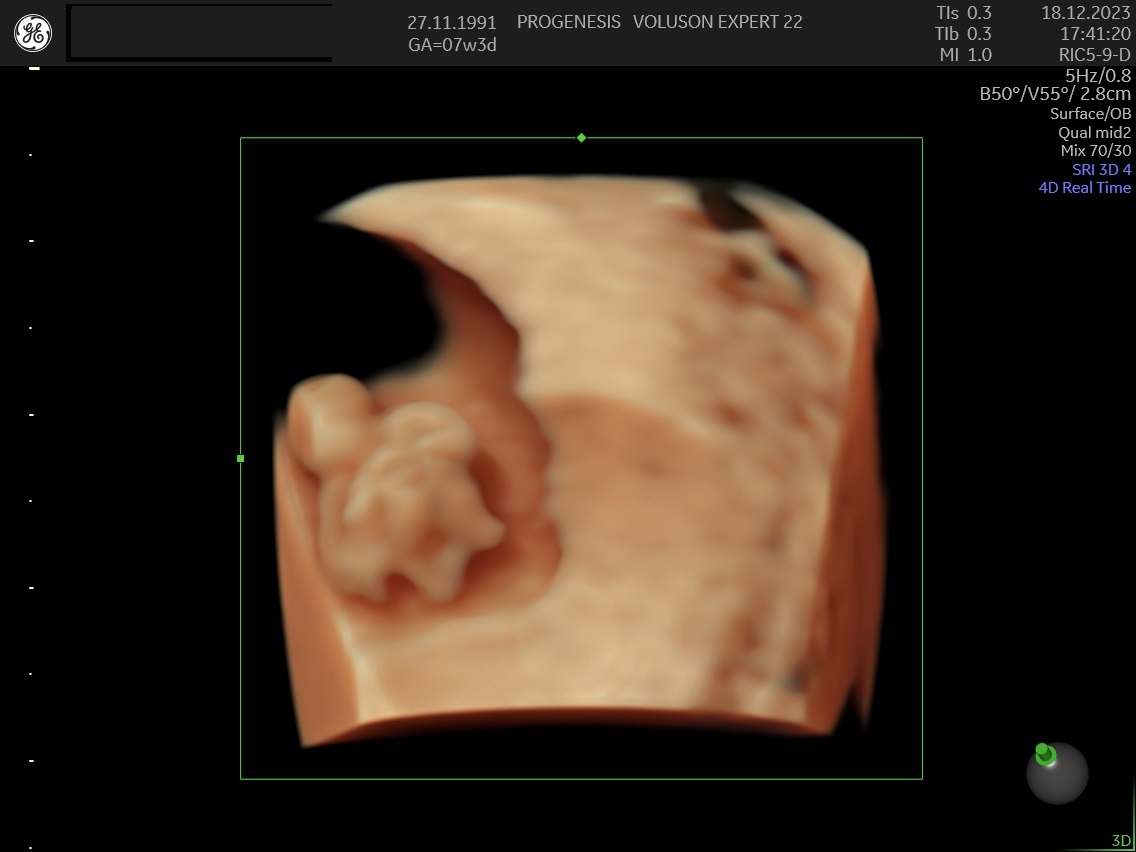

Υπερηχογράφημα Αρχόμενης Κύησης

(6-11 εβδομάδων)

Σκοπός της εξέτασης είναι να επιβεβαιώσουμε ότι υπάρχει φυσιολογικά εξελισσόμενη κύηση μέσα στη μήτρα, αναγνωρίζοντας έμβρυο με καρδιακή λειτουργία, και  αποκλείοντας την εξωμήτριο  κύηση.

Επιπλέον, αναγνωρίζεται ο αριθμός των εμβρύων, έχουμε μία πρώτη εκτίμηση της ηλικίας κύησης καθώς και της χοριονικότητας (εάν δηλαδή τα έμβρυα μοιράζονται τον ίδιο πλακούντα) στη περίπτωση της πολύδυμης κύησης.